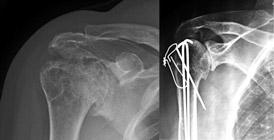

Protesi di spalla

Un’altra causa di dolore alla spalla è costituita dall’artrosi, una patologia cronico-degenerativa che porta progressivamente a dolore costante e limitazione funzionale.

Sebbene la spalla non sia un’articolazione sottoposta a carico, fattori influenti sull’evoluzione della patologia sono costituiti da sport o lavori usuranti su tale articolazione, pregresse tendinopatie o rotture della cuffia dei rotatori.

Generalmente i sintomi iniziano verso i 55-60 anni e la patologia si sviluppa lentamente peggiorando nel tempo.

Le terapie fisiche (strumentali e/o riabilitative) cosituiscono efficaci rimedi nel miglioramento dei sintomi, tuttavia quando questi trattamenti non sono efficaci la chirurgia protesica può diventare l’unica alternativa.

Sebbene la sostituzione protesica della spalla sia meno comune rispetto a quella dell’anca o del ginocchio, essa è altrettanto efficace per alleviare il dolore articolare.

Esistono diversi tipi di protesi che hanno indicazioni diverse; il Chirurgo valuterà attentamente le condizioni cliniche e patologiche e sceglierà il tipo di protesi in base a diversi fattori.